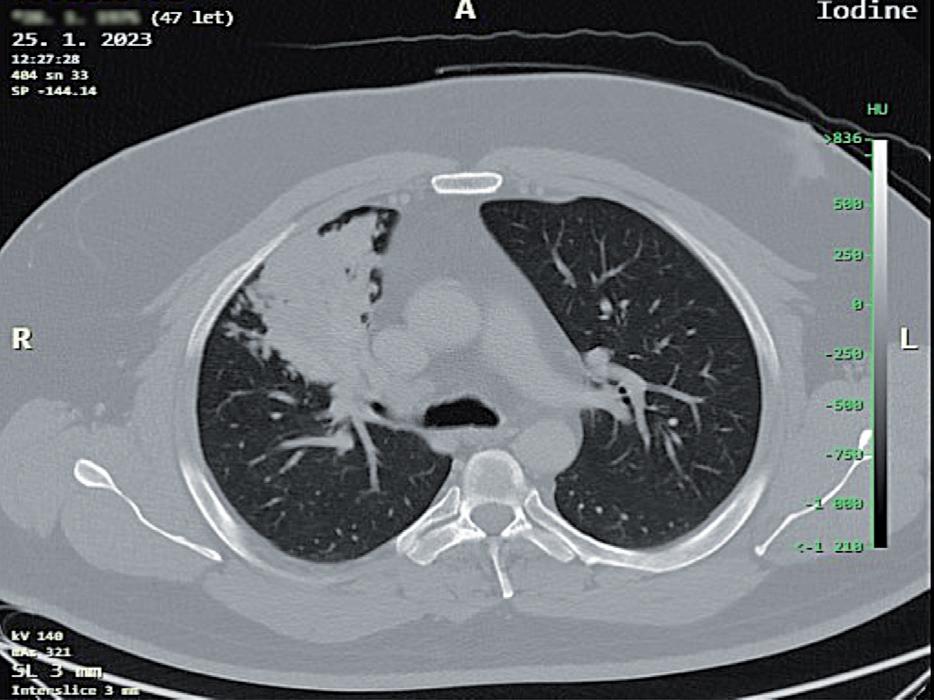

Velký nádor nebo infiltrát (obr. 3.4) zhoršuje možnost manipulace s plící a přístup k důležitým strukturám. To může být kritické pro vznik a ošetření komplikujících poranění. Malý intraluminální karcinoid, ale s postob strukční pneumonií a infiltrací laloku je lépe odoperovat otevřeně z torakotomie. Přílišná snaha o vytažení nádoru větších rozměrů z minitorakotomie, například s použi tím techniky nastřihávání resekátu, vede k poškození preparátu pro správné patologické posouzení. Při užití excesivní síly tahu za extrakční vak s resekátem zvyšuje me riziko jeho roztržení a implantace nádorových buněk do do operační oblasti a minitorakotomie. Resekovaná plíce není vždy dokonale desuflovaná, což dále zvětšuje

obr. 3.4 Adenokarcinom plicní po neoadjuvanci indikovaný k operačnímu řešení u 65letého muže na CT (a) a PET CT (b) obraze je masou nádoru natolik objemný (v největším rozměru prakticky 10 cm), že postihuje více než objem jednoho segmentu horního laloku levé plíce. Pro bezpečné vyjmutí resekátu nádoru, laloku plicního, je v tomto případě nutná regulérní torakotomie. Nádor dosahuje blízkosti odstupu tepenných větví pro horní lalok. Takový nález není vhodný pro videoskopické řešení. Výkon z torakotomie v takových případech upřednostníme. Po otevřené horní lobektomii vlevo a kompletní spádové lymfadenektomii nebylo patologem u pacienta nalezeno žádné nádorové postižení uzlin

obr. 3.5 Příklady nádorů, které jsou k videotorakoskopickému operování z anatomického hlediska sice méně vhodné, ale videotorakoskopická operace by měla být proveditelná; a) nemalobuněčný plicní karcinom o větším průměru než 6,5 cm s centrální kavernou, abscesem, u 58letého muže, navíc s těsným vztahem k hrudní stěně, b) endobronchiální karcinom s přetrvávající objemnou postobstrukční infiltrací S3 u 47letého muže. Pohled na indikaci videotorakoskopického přístupu je relativní. Ovlivňuje jej technické vybavení, zkušenost i naturel operujícího. Pokud pomineme velikost nádoru nad 6 cm (a), a tím možnou potřebu větší minitorakotomie, pak videorobotický přístup by zde mohl být naopak výhodou při oddělování nádoru od hrudní stěny nebo dokonce při její resekci